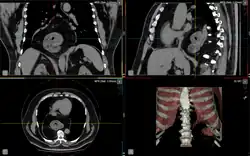

Die paraösophageale Hiatushernie (siehe Abbildung, Buchstabe D) zeichnet sich aus durch die anatomisch korrekte Lage des unteren Ösophagussphinkters (Schließmuskel der Speiseröhre) und dessen uneingeschränkte Funktion. Ein Teil des Magens schiebt sich jedoch von unten in den Brustraum. In der äußersten Form dieser Hiatushernie kann auch der ganze Magen oberhalb des Zwerchfells liegen (Upside-Down-Stomach oder Thoraxmagen). Im klinischen Verlauf beginnt die paraösophageale Hiatushernie mit einem asymptomatischen Stadium. Es folgt das unkomplizierte Stadium, mit Aufstoßen und Druckgefühl in der Herzgegend. Diese Symptome treten vor allem nach der Nahrungsaufnahme auf. Danach kommt es zum Komplikationsstadium mit Passagestörungen, Inkarzerationen, Geschwüren und Blutarmut infolge chronischer Blutungen.